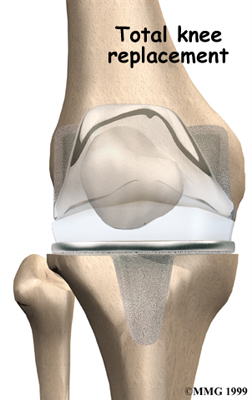

Artificial Knee Replacement

An artificial knee replacement is the ultimate solution for advanced knee OA.

Surgeons prefer not to put a new knee joint in patients younger than 60. This is because younger patients are generally more active and might put too much stress on the joint, causing it to loosen or even crack. A revision surgery to replace a damaged prosthesis is harder to do, has more possible complications, and is usually less successful than a first-time joint replacement surgery.

Related Document: Fyzical Sarasota-Cattlemen's Guide to Artificial Joint Replacement of the Knee